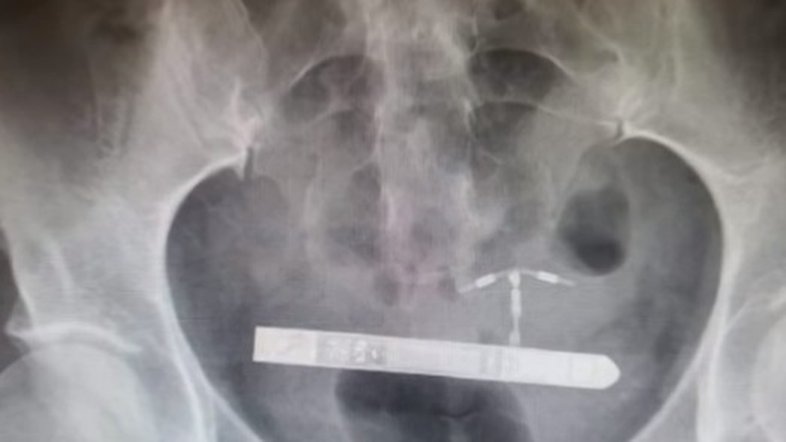

Vibrador alojado ao lado da bexiga Foto: Reprodução YouTube

“Nós da equipe médica não conseguimos encontra-lo na vagina”, relembrou o ginecologista Greg Marchand. Em seguida, a mulher passou por um exame de raio x. “Fiquei surpreso quando percebi que ele estava na bexiga da paciente”.